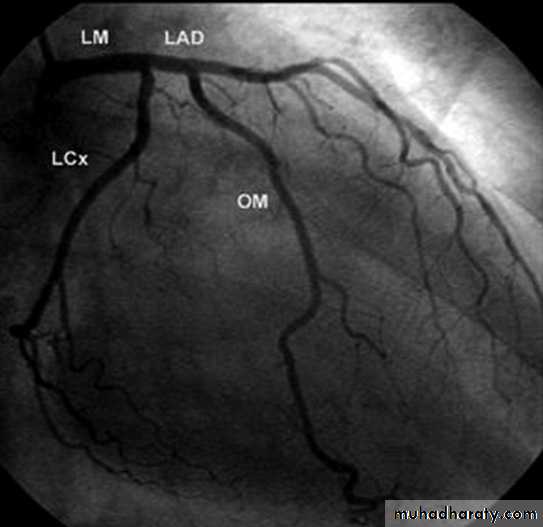

Angiography of coronary vessels